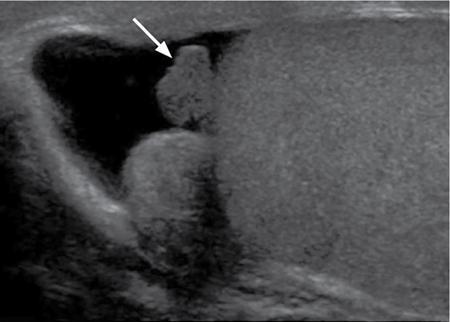

Prostatic cysts